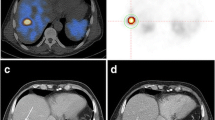

PET/CT Imaging, Imaging Interpretation

As a prerequisite for treatment initiation, all patients had to demonstrate sufficient uptake in pre-therapeutic SSTR-PET computed tomography (CT) [18, 19], i.e., lesional uptake higher than physiological liver uptake [21]. A mean of 132 ± 35.7 MBq (3.6 ± 0.9 mCi; range, 72–185 MBq, 1.9–5 mCi) of [68Ga]DOTATATE/-TOC (n = 27, [68Ga]DOTATATE and n = 4, -[68Ga]DOTATOC) was administered intravenously. After 60 min, imaging was performed using the following scanners: Bonn, Biograph 2 PET/CT (Siemens Medical Solutions, Erlangen, Germany); Wuerzburg, Biograph 64 (Siemens Medical Solutions, Erlangen, Germany); Munich, Gemini TF PET/CT (Philips Medical, Eindhoven, Netherlands) or Siemens Biograph 64 (Siemens Medical Solutions, Erlangen, Germany); Hannover, Biograph 2 (Siemens Medical Solutions, Erlangen, Germany). System spatial resolutions are 4.8 mm for the Gemini TF, 4.4 mm for the Biograph 64, and 9.3 mm for the Biograph 2 [22,23,24]. All data was reconstructed using iterative algorithms implemented by the manufacturer and depending on the routine protocol of the different medical centers. Scatter and attenuation correction was performed based on the different transmission data [13]. To allow for valid pooling of the results between Siemens and Philips PET/CT scanners, phantom studies based on the National Electrical Manufacturers Association NU2-2001 standard were conducted in Munich. According to a recent published study investigating the robustness of TF in GEP-NET patients using SSTR-PET in a multicentric setting, the following TF were taken into account [25]: from the gray-level co-occurrence matrix (Entropy, Homogeneity), from the gray-level run length matrix (high gray-level run emphasis (HGRE)), and from the gray-level size zone matrix (intensity variation, high gray-level zone emphasis (HGZE), zone length non-uniformity (ZLNU), short-zone high gray-level emphasis (SZHGE), zone percentage (ZP)). In addition, metabolic tumor volume (MTV) and total receptor expression (TRE) were assessed. Lesions were identified by reviewing the SSTR-PET, CT, and fused hybrid imaging by board-certified nuclear medicine physicians. In case of multiorgan involvement, a maximum of three lesions per organ (largest in size and metabolically most active lesion) was segmented. A manual segmentation method was preferred in order to exclude adjacent physiological SSTR-avid structures on PET/CT images [26]. TF analysis was performed by using the Interview Fusion Workstation (Mediso Medical Imaging Systems Ltd., Budapest, Hungary) [13]. As previously described, CT images were available only for localization and not used to guide delineation of the VOI [27]. Further, conventional PET parameters (SUVmean/max, metabolic tumor volume (MTV) and tissue receptor expression (TRE = MTV × SUVmean)) were also investigated [13]. The radiotracer concentration in the ROIs was normalized to the injected dose per kilogram of patient’s body weight to derive the SUVs. For the assessment of TF, 162 volume of interest (median, 5, range, 1–12 per patient) were manually segmented. In the majority of the cases (22/31, 71 %), at least four lesions were investigated. Metastases with an MTV smaller than 10 cm3 were excluded [28].

In ROC analysis of TF, entropy demonstrated a significant predictive ability for OS (cutoff = 6.7, AUC = 0.71, p = 0.02) with an accuracy of 71 %. Increasing entropy could predict longer survival (> 6.7, OS = 2.5 y, 17/31), whereas less entropy portended inferior outcome (< 6.7, OS = 1.9 y, 14/31, Table 2, Supplementary Table a: see electronic supplementary material (ESM)). All the investigated conventional PET parameters (SUVmean/max, MTV, TRE) failed in response prediction (Supplementary Table b).

In Cox hazard analysis, entropy and intensity variation demonstrated significance for OS (p < 0.05, respectively). For PFS, none of the investigated conventional PET parameters (SUVmean/max) or other TF were significant. Regarding clinical parameters, the cumulative administered dose reached significance for OS (p = 0.04, r = 0.37) and Ki67 for PFS prediction (p = 0.002, r = − 0.54). For those patients below the ROC-derived threshold for entropy, the RR of cancer-related death after PRRT was 2.73 (n = 31, CI 1.07–7.01; p = 0.04) (Fig. 1, Supplementary Table c in ESM).

Higher entropy values are related to superior outcome in our study. A multivariate Cox analysis corroborated these findings: the RR for cancer-related death for those patients below the ROC-derived threshold of entropy indicated an almost threefold increased mortality compared to that for the low-risk group (Fig. 1). These results are contrary to findings in [18F]FDG PET studies investigating TF in pancreatic ductal carcinoma or non-small cell lung cancer (low entropy associated with longer OS) [41, 42]. Understandably, results from [18F]FDG PET in highly metabolically active tumors cannot be directly transferred to SSTR-PET; however, these findings emphasize the value of tumor heterogeneity assessment.